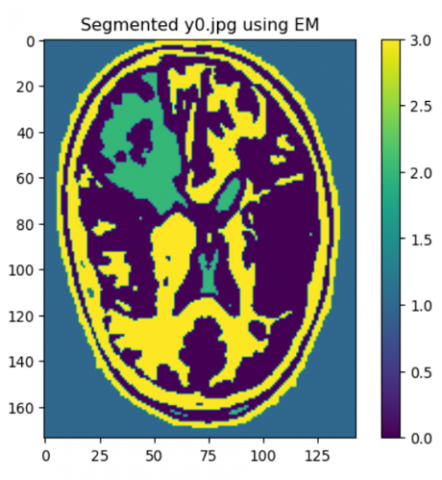

Algorithm expectation-maximization

Step 5: Visualize the EM(Expectation-Maximization) algorithm result.

Figure 5 shows the implementation of expectation-maximization algorithm to highlight the brain tumor.

Figure 5. Results of expectation-maximization algorithm for segmentation